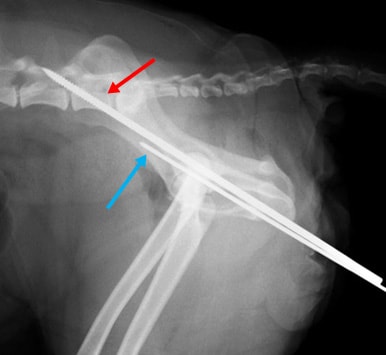

股関節脱臼① 関節包再建術とDeVitaピン法と伸縮性創外固定装置を併用して整復した一例

関節包再建術後、大腿骨頭の背側脱臼を防ぐためのDeVitaピンを挿入します。(赤矢印)

|

DeVitaピン(赤矢印)とクロスピン(青矢印)を挿入後、大腿骨の外旋を防ぎ、